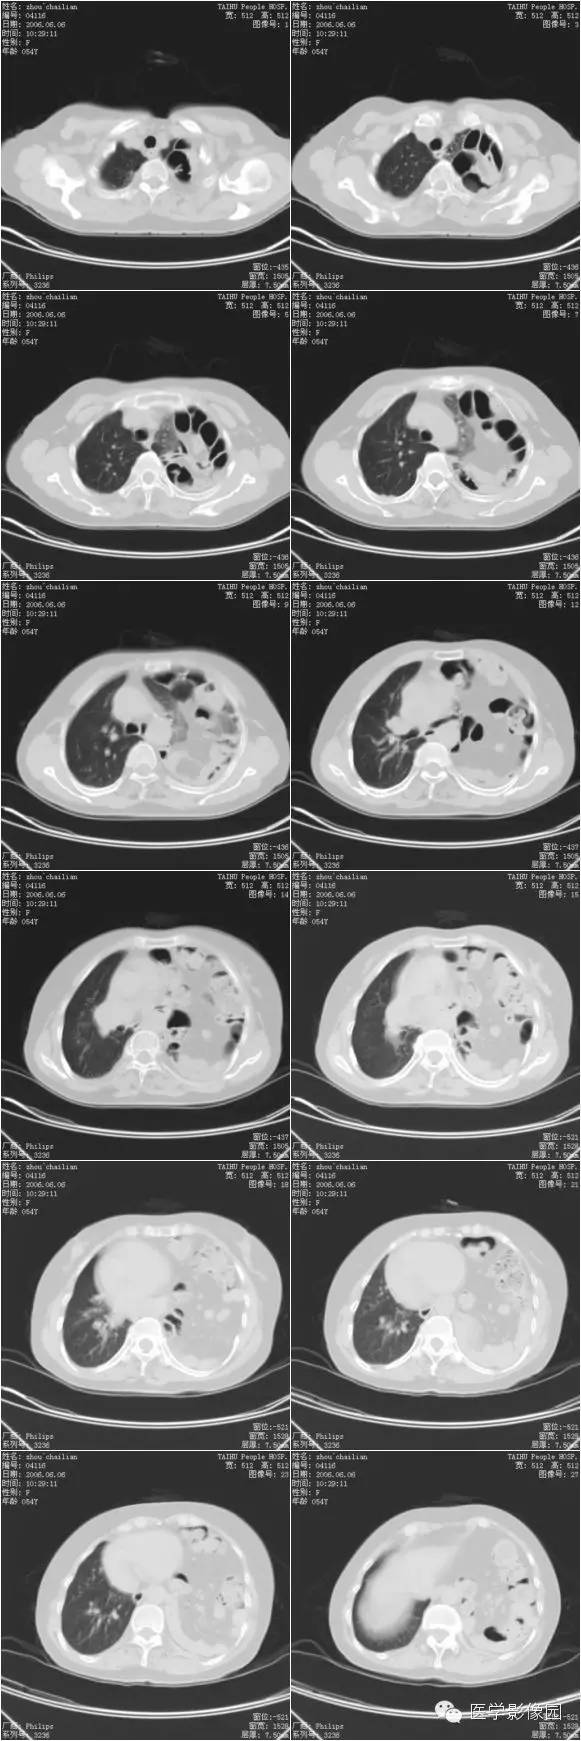

纵隔大细胞神经内分泌癌1例CT影像